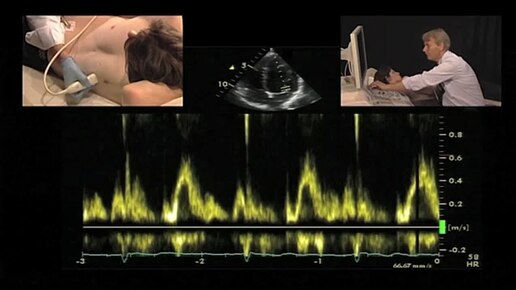

7. Doppler

ЭХОКГ